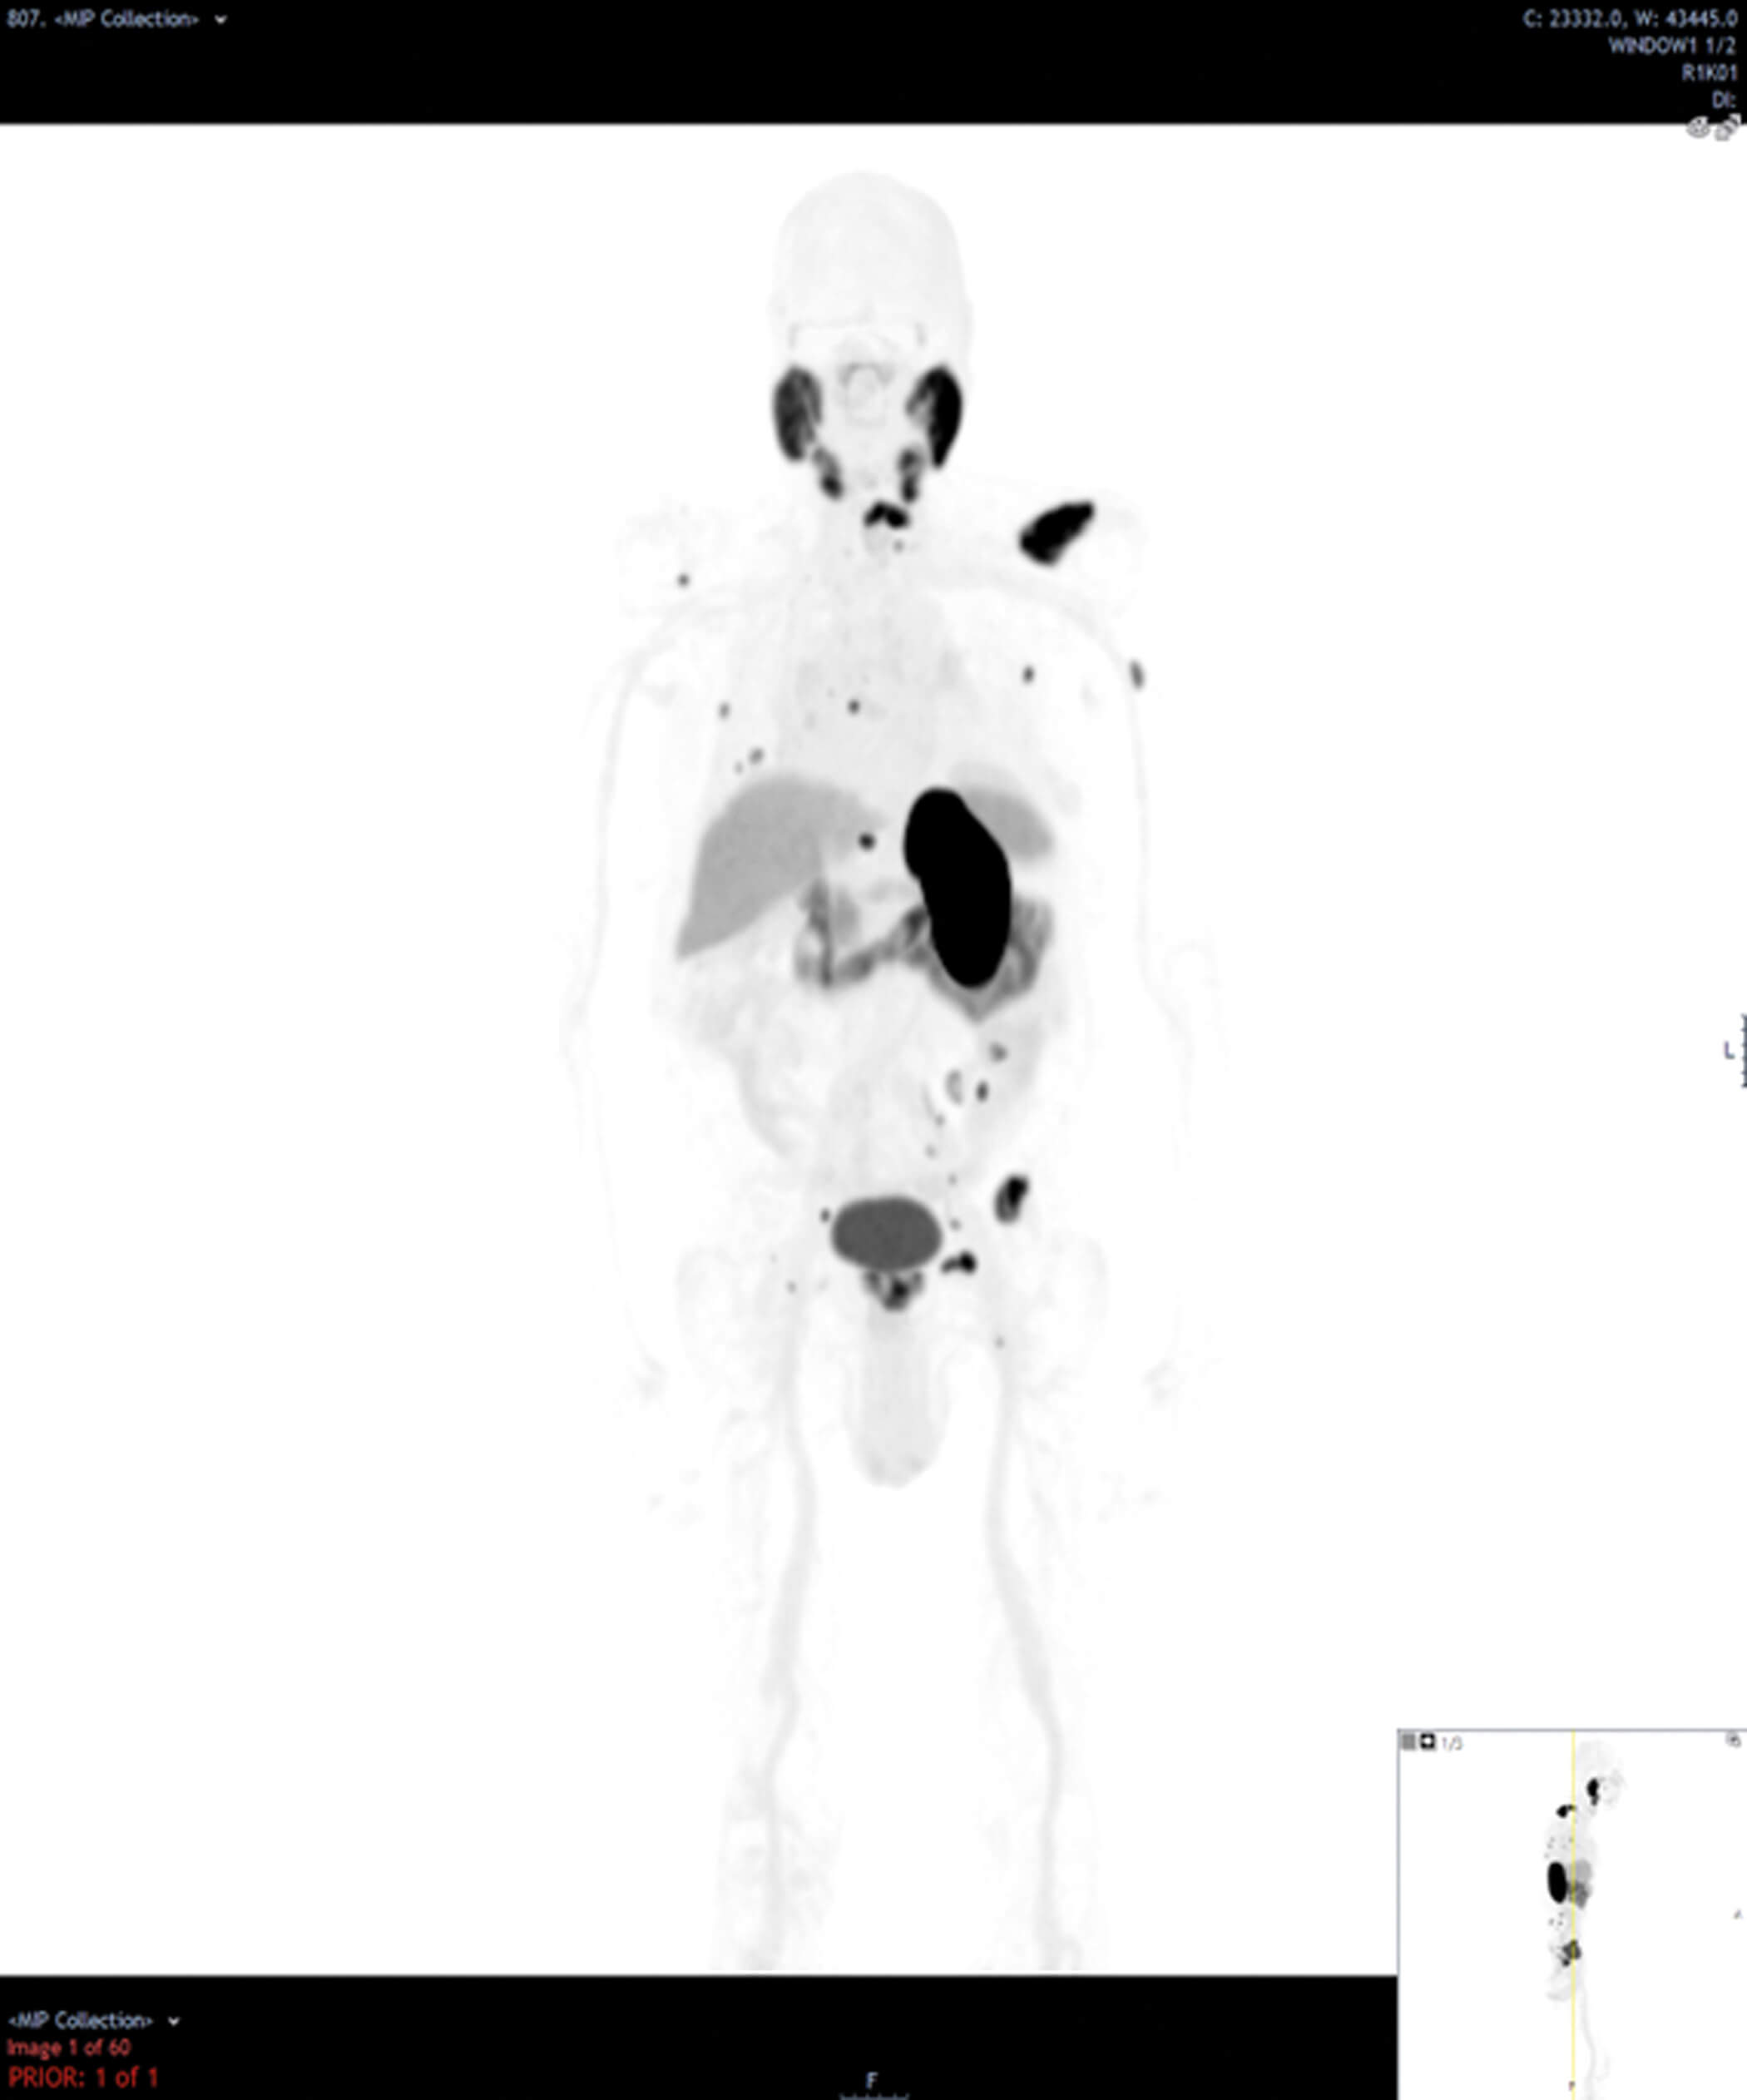

- What type of scan is shown in Figures 2 and 3? What are the indications for this modality in the context of prostate cancer? What do the images show? What is its sensitivity and specificity?

4. This is a prostate-specific membrane antigen-positron emission tomography (PSMA-PET) scan. Figure 2 is a maximum intensity projection (MIP) image showing PSMA uptake in the prostate, internal iliac lymph nodes and skeletal metastases. Figure 3 is an axial fused PET-CT image demonstrating uptake in the left seminal vesicle, a left internal iliac lymph node and the left superior pubic ramus.

PSMA is a membrane glycoprotein that is expressed at 100-1000-fold higher levels in prostate cancer as compared with healthy prostate tissue. PSMA PET scans use molecules (ligands) with radioactive tracers that specifically bind to PSMA enabling rapid accumulation in viable prostate cancer cells. There are several ligands including Galium-68 (68Ga), Fluorine-18 (18F) and Piflufolastat F-18 (18F-DCFPyL).

This overexpression of PSMA glycoprotein in prostate cancer cells is stipulated to be better at identifying lymph node and bone metastases than other imaging modalities. However, PSMA can also be expressed in other conditions thus sensitivity is 89-97% but specificity is reported around 40-56% [3]. The indications for PMSA-PET scans as per the European Association of Urology (EAU) guidelines include initial staging in intermediate and high-risk prostate cancer if available [3], and for suspected prostate cancer recurrence.